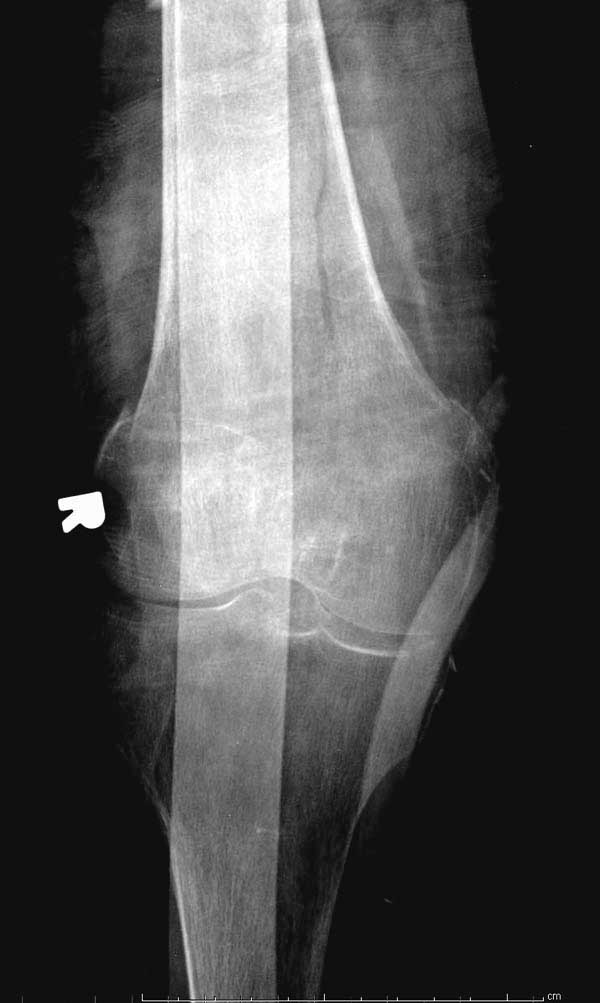

No comment.

Бедная бабушка!

Неужели фиксация протеза бесцементная? Да и чашка не запрессована как надо.Грустно(

Эт -ж биполяр:)) Ножка цементная. Страйкеровский Exeter.1

биполярный эндопротез все же не лучший выбор для данной ситуации.судя по снимкам мышечные прикрепления на вертелах утрачены.Возможно здесь подошла бы более стабильная конструкция.Ваше мнение?

а куда делся фрагмент большого вертела? Очевидно,

Если среднеягодичная мышца не рефиксирована, то ничто не держит протез во впадине и это закономерный результат.

Третья операция-продолжения усилии “синьорами пэрами” по разрушению нормальной анатомии. Крест на головку! По видимому возраст позволяет биполярную конструкции, и при дефекте calcar пошли на обычный цементный. Ягодичные мышцы потеряли связь с вертелом, т.е. отсутствует верхний удержатель, и результат “a Big Screw Up!” Снимки вызывают головокружение!

Если хирурги не устали от своих “творчеств”, тогда можно ре-оперировать с calcar replacement stem, и собрать остаток ягодичных мышц. Глубина и отстутствие артроза позволяет применить любой, биполярный или тотальный, хотя принять решение можно после ревизии ацетабулума.